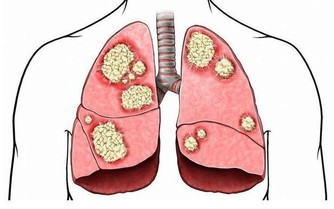

痘痘的影響 痤瘡俗稱為青春痘,它總會在你毫無防備的情況下襲擊你的臉龐。它其實是由於皮脂腺分泌過多油脂,加上毛孔內毛髮和老死角質的堆積,使油脂和細菌附著,引發皮膚紅腫的反應。其常見於青少年,但近些年成人痘也成為不容輕視的皮膚問題。青春痘一旦處理不當留下痘印痘疤就會對外貌造成嚴重影響。

痘痘、痘印產生的過程